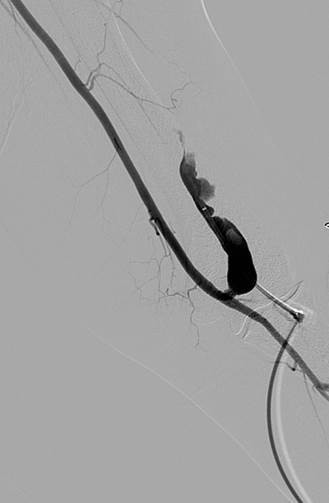

Trombectomía de fístula AV braquiocefálica izquierda

Venograma central inicial que confirma la permeabilidad de las venas centrales.

Estenosis subyacente en el arco de la vena cefálica responsable de la trombosis.

Fistulograma tras la primera pasada con un catéter DVX de AngioJet (N. B.: no se usaron trombolíticos).

Fistulograma tras la segunda pasada con un catéter DVX. Se ha identificado otra estenosis hacia la mitad de la FAV.

Se precisó la colocación de stents en la fístula cefálica y en el arco de la vena cefálica debido a un retroceso elástico considerable tras la angioplastia de estas constricciones.

También se identificó una constricción anastomótica.

Tras la angioplastia de la constricción anastomótica.